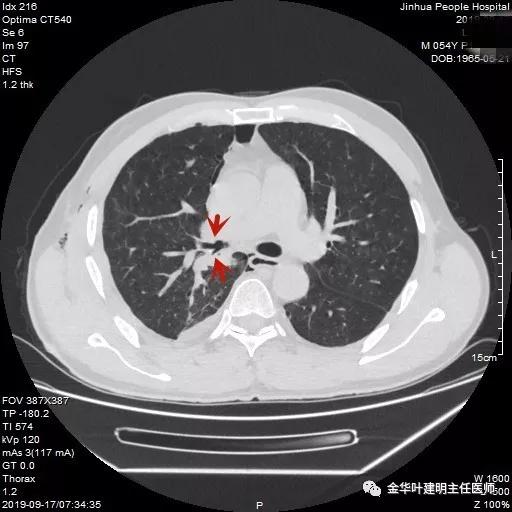

术后第8天,复查胸部CT如下,见上叶复张良好,支气管吻合口通畅,恢复非常好,当天下午予以出院休养了,与平时胸腔镜下肺叶切除的时间相当。术后石蜡病理支气管旁淋巴结有1枚转移,纵隔淋巴结均阴性。我也在想如果当时勉强镜下吻合,会不会这么顺利呢?不管如何,病人安全,吻合满意,恢复顺利,这是最重要的!

蓝色区域为右主支气管与右上叶支气管吻合处

红色箭头所示较小的右上支气管与较粗的右主支气管,似乎有点套入的感觉

红色箭头所示吻合口,非常通畅,右上叶膨胀非常好